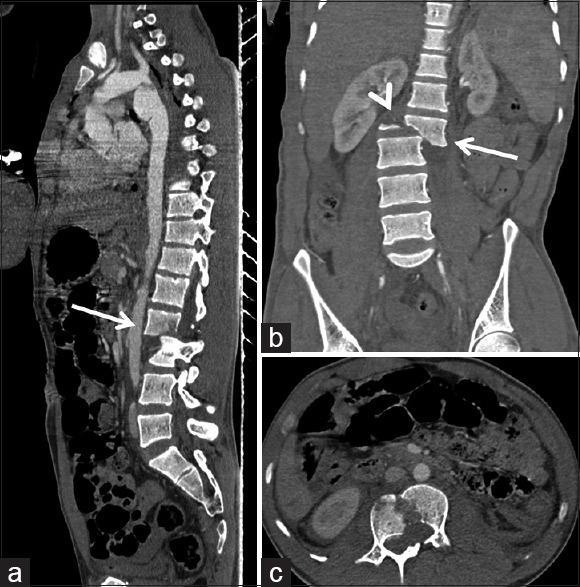

Spinal cord injury is one of the most debilitating injuries in patients with spinal trauma. Cord injury may range from simple cord edema to frank transection. Cord transection is the most severe form of cord injury as it results in complete and irreversible loss of all neural functions. Generally, it is a result of unstable spinal fractures with associated spondylolisthesis or spondyloptosis. Generally, the level of cord transection corresponds to the level of spinal fracture/spondylolisthesis. However, here we are presenting a case having a traumatic spinal fracture with spondylolisthesis where the level of cord transection was much higher than the level of the spinal fracture. Due to the traumatic traction, the cord distal to transection is displaced inferior leaving behind a long segment of the empty thecal sac.

脊髓损伤是脊柱创伤患者中最使人衰弱的损伤之一。脊髓损伤的范围可从单纯的脊髓水肿到完全横断。脊髓横断是脊髓损伤最严重的形式,因为它会导致所有神经功能完全且不可逆转的丧失。一般来说,它是不稳定脊柱骨折合并椎体滑脱或脊柱后凸的结果。通常,脊髓横断的水平与脊柱骨折/椎体滑脱的水平相对应。然而,在此我们报告一例伴有椎体滑脱的创伤性脊柱骨折病例,其中脊髓横断的水平远高于脊柱骨折的水平。由于创伤性牵引,横断部位远端的脊髓向下移位,留下一段长长的空硬膜囊。